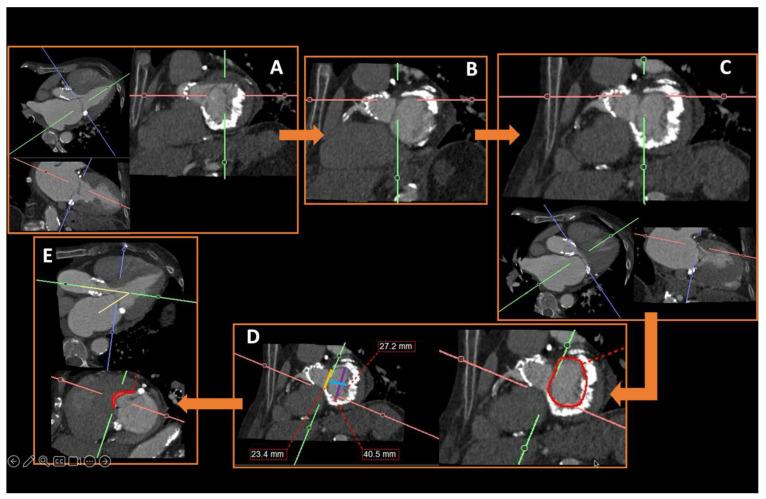

在过去十年中,多项试验和观察性研究证实,微创心脏介入治疗作为各种心脏病的可行治疗选择是有效的。在某些患者群体中,用于严重主动脉瓣狭窄的经导管技术已迅速成为外科主动脉瓣置换术的替代方法。此外,针对影响其他心脏瓣膜(如二尖瓣)的病症,非手术治疗选择也有所增加。这些新兴的微创介入治疗补充了已成熟的血管内技术,用于治疗心房颤动患者的房间隔缺损封堵、左心耳封堵和肺静脉隔离等疾病。鉴于这些手术的非手术性质以及缺乏对目标解剖结构的直接可视化,这些手术严重依赖精确的术前放射影像学检查,以实现最佳的患者选择和手术成功。本文基于作者的专家意见和详尽的文献研究。本手稿回顾了最常用的微创心脏介入治疗,强调了术前成像的基本信息以及放射学报告中必须包含的关键方面,以减少潜在并发症。准确的术前成像对于确保微创心脏介入治疗的安全有效至关重要,这突出了放射科医生在这些患者术前检查中的重要性。